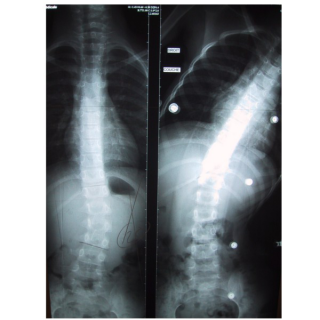

Dos / rachis / thorax Corsets de traitement scoliose Corset nocturne en hyper-correction dit de "Charleston"

• Scoliose idiopathique chez l’adolescent

• Scoliose à courbure simple ou double

- L'enfant est placé en inflexions latérales, en hypercorrection

- L’enfant est placé en inflexions latérales, en hypercorrection

- Cette correction à «mi-temps est parfois suffisante pour contenir avec succès une déviation scoliotique